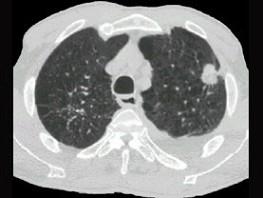

问题 女,64岁,胸背疼痛一周,CT检查如图,最可能的诊断为 ( )

选项 A、左上肺单发性转移癌 B、左上肺错构瘤 C、左上肺周围型肺癌 D、左上肺炎性假瘤 E、左上肺结核球

答案 C